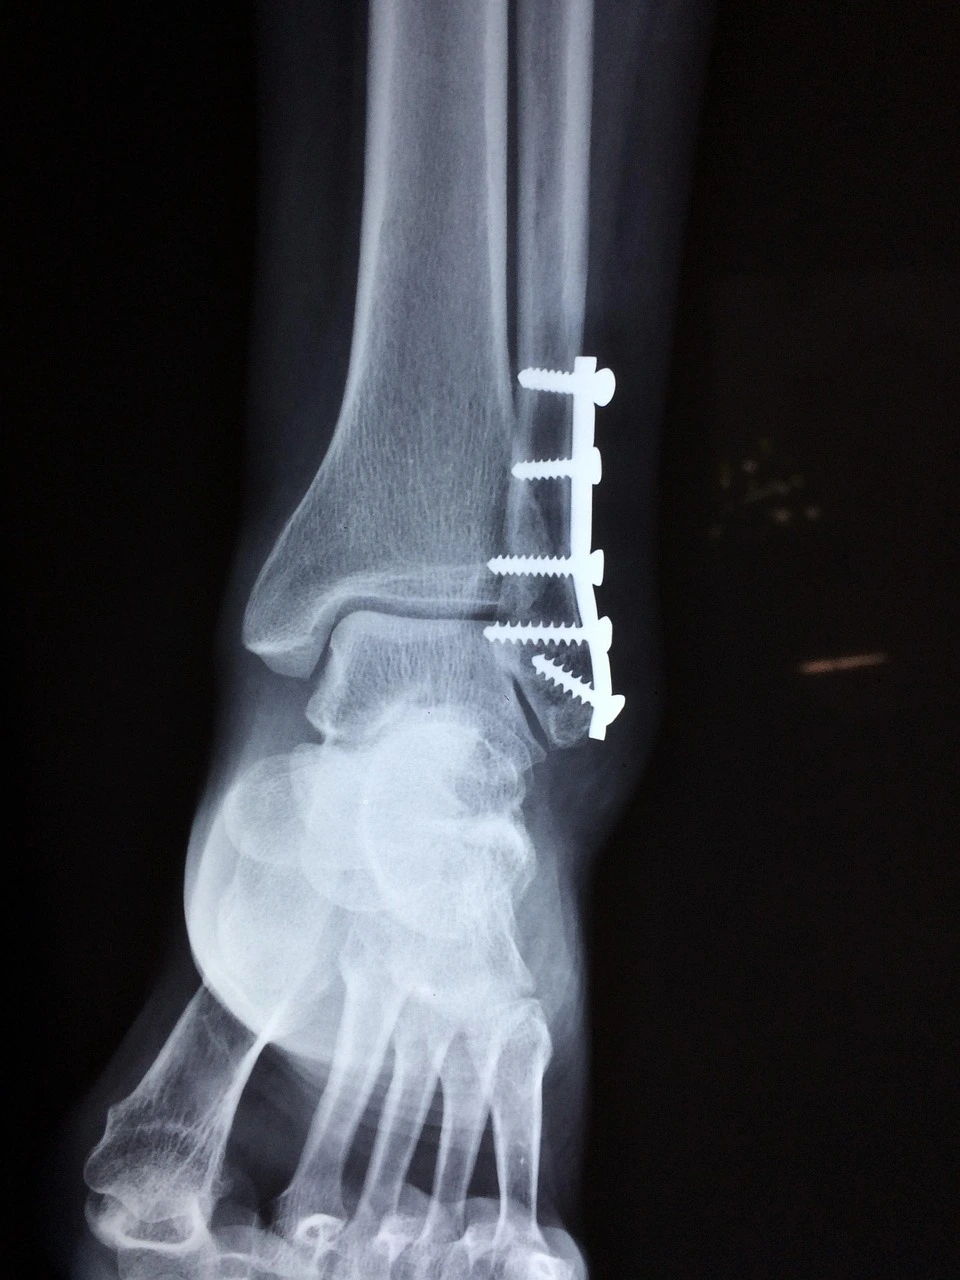

이번이 몇 번째 병원신세인가 생각해 보니... 지난번 축구 경기에서는 상대 선수의 공을 가로채려다 무리한 태클로 상대선수 발목 골절을 입히고 레드카드를 받았고 본인도 오른쪽 발목 아킬레스건을 다쳤다. 반칙으로 퇴장을 당하고 부상까지 얻었으니 동료들의 원성이 높았고 누구 하나 병문안도 오지 않았다.